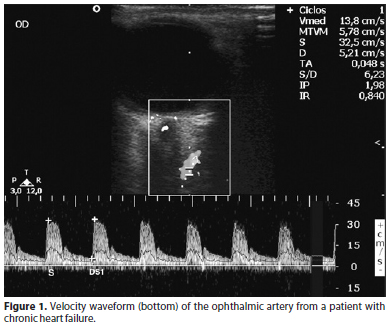

Once the waveforms of the ophthalmic artery were obtained, the values of systolic velocity, diastolic velocity and resistance index were calculated using the automatic algorithm of the machine (Figure 1). Three measurements were taken from all patients by each radiologist, and the mean value was considered for the analysis.

This study evaluated the ophthalmic artery blood flow in patients with heart failure. No similar study was found in the literature regarding this form of evaluation. Low cardiac output is associated with compensatory mechanisms of peripheral vasoconstriction in attempt to maintain satisfactory blood pressure and minimum perfusion to critical tissues such as the heart and brain(17,26). On the other hand, the excessive vasospasm/vasoconstriction of the ocular vessels may be related to a reduction in the perfusion and tissue death at the optic nerve head(6). Therefore, patients with CHF could present hemodynamic alterations of the ocular microvasculature and a higher risk of developing glaucoma. The color Doppler imaging of the ophthalmic artery with the velocity waveform in function of the heart cycle offers important information regarding hemodynamic pathophysiology.